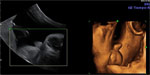

Ecografía 4D del tercer trimestre: Bebé del sexo masculino

Ecografía 4D de un feto del sexo masculino en el tercer trimestre de embarazo

El examen ecográfico en 4D no deja lugar a dudas: se trata de un varón –vemos su aparato genital en primer plano- con las piernas flexionadas hacia arriba. El bebé se encuentra en las últimas semanas de gestación.